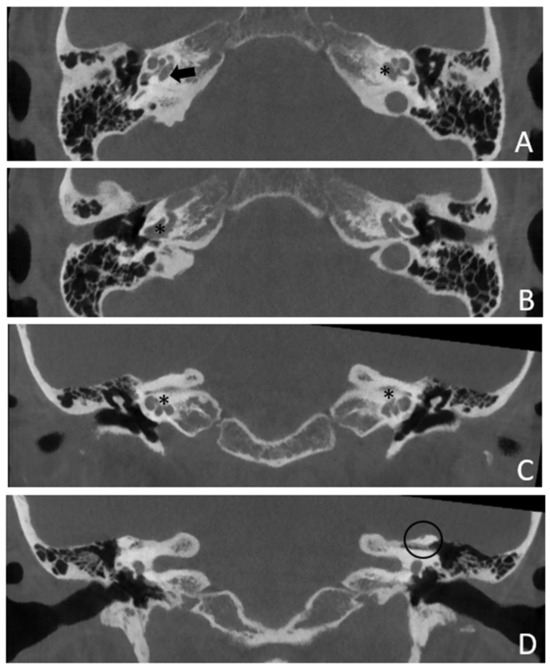

Within a few years, both ears showed a worsening of bone threshold to SNHL bilaterally. In 2017 (27 years since diagnosis) she developed profound SNHL with left-sided anacusis and underwent cochlear implantation in the left ear. CT and MR images showed a large cavity around the basal turn of the cochlea and massive osteorarefaction around the cochlea (‘double ring’ sign). The cavity appeared to contain cerebrospinal fluid but did not communicate with the cochlear lumen (Figure 1 and Figure 2).

Figure 1. CT images of patient #1 with osteogenesis Imperfecta. (A,B), right side in axial plane. (C,D), right side in coronal plane. (E,F), left side in axial plane. (G,H), left side in coronal plane. A pericochlear cavity is visible in all figures; arrows indicate its origin from the IAC. Asterisks indicate extension of osteorarefation into the cochlea.